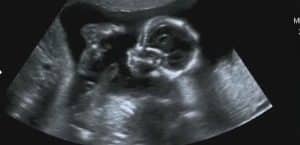

The evaluation of first-trimester ultrasound mainly involves diagnosing IUP, estimating gestational age, and measuring nuchal thickness. During an examination, the uterus, cervix, and the adnexa are inspected to check for the position of the gestational sac and the presence of a yolk sac. Beta-human chorionic gonadotropin (b-hCG) levels set up have been found to be consistent with standard anticipated fetal sonographic appearances and help in assessing the likelihood of pregnancy continuation.

Some more important observations are visibility of yolk sac at 5-6 weeks of pregnancy and embryo at 6+ weeks of pregnancy. The fetal heart activity, the number, location, and chorionicity should be documented, especially if there are twins at pregnancy. Other findings, including a corpus luteum cyst or uterine fibroid(s) must also be documented.

Ultrasound is also useful in the identification of abnormal pregnancies, for instance, embryo demise characterised by CRL of 6mm and no fetal cardiac activity, ectopic pregnancy or even severe fetal anomalies such as anencephaly. Also, the first-trimester ultrasound is employed for the aneuploidy biomarker, including those such as nuchal translucency, absent nasal bone, and other Doppler signs.